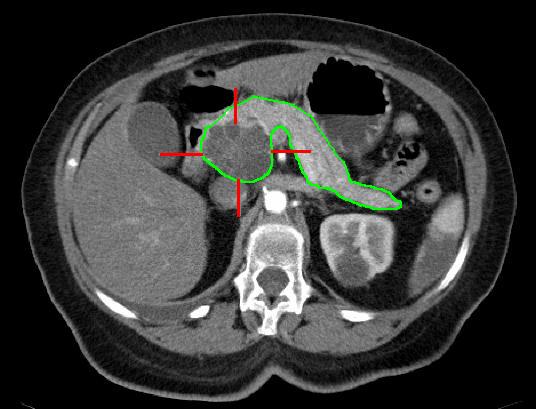

Computertomographie

Die Computertomographie ist häufig das erste diagnostische Mittel im Rahmen der Untersuchung bei Tumoren der Bauchspeicheldrüse. Nicht selten ist dies bereits vor dem ersten Termin in unserer Sprechstunde bereits vom Hausarzt angemeldet und in einem Röntgen-Institut durchgeführt worden.

Anhand dieser Bilder und Befunde kann eine erste Aussage über die Lage des Tumors und der Möglichkeit und das Ausmass einer Operation getroffen werden.